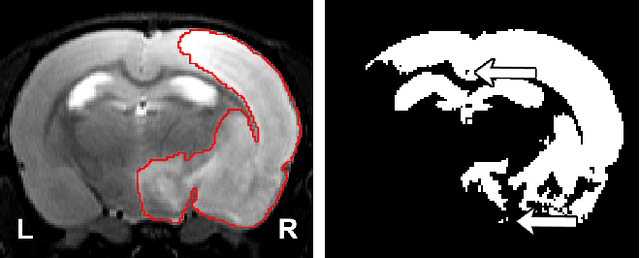

Abstract:We present MedicDeepLabv3+, a convolutional neural network that is the first completely automatic method to segment brain hemispheres in magnetic resonance (MR) images of rodents with lesions. MedicDeepLabv3+ improves the state-of-the-art DeepLabv3+ with an advanced decoder, incorporating spatial attention layers and additional skip connections that, as we show in our experiments, lead to more precise segmentations. MedicDeepLabv3+ requires no MR image preprocessing, such as bias-field correction or registration to a template, produces segmentations in less than a second, and its GPU memory requirements can be adjusted based on the available resources. Using a large dataset of 723 MR rat brain images, we evaluated our MedicDeepLabv3+, two state-of-the-art convolutional neural networks (DeepLabv3+, UNet) and three approaches that were specifically designed for skull-stripping rodent MR images (Demon, RATS and RBET). In our experiments, MedicDeepLabv3+ outperformed the other methods, yielding an average Dice coefficient of 0.952 and 0.944 in the brain and contralateral hemisphere regions. Additionally, we show that despite limiting the GPU memory and the training data to only three images, our MedicDeepLabv3+ also provided satisfactory segmentations. In conclusion, our method, publicly available at https://github.com/jmlipman/MedicDeepLabv3Plus, yielded excellent results in multiple scenarios, demonstrating its capability to reduce human workload in rodent neuroimaging studies.